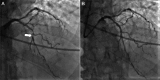

Case summary: We present a patient with coronary artery disease who developed an episode of ventricular fibrillation during a cardiovascular magnetic resonance examination. The arrhythmia appeared immediately after the injection of a contrast agent during a quantitative myocardial perfusion sequence at rest, with no stressor agent involved.

Discussion: To our knowledge, this is the first episode of ventricular fibrillation documented with simultaneous electrocardiographic, physiological recordings, and quantitative myocardial perfusion data. Such unique information allowed for a comprehensive analysis of the sequence of facts preceding the final arrhythmia and, in consequence, provided a well-reasoned conclusion on its mechanism.